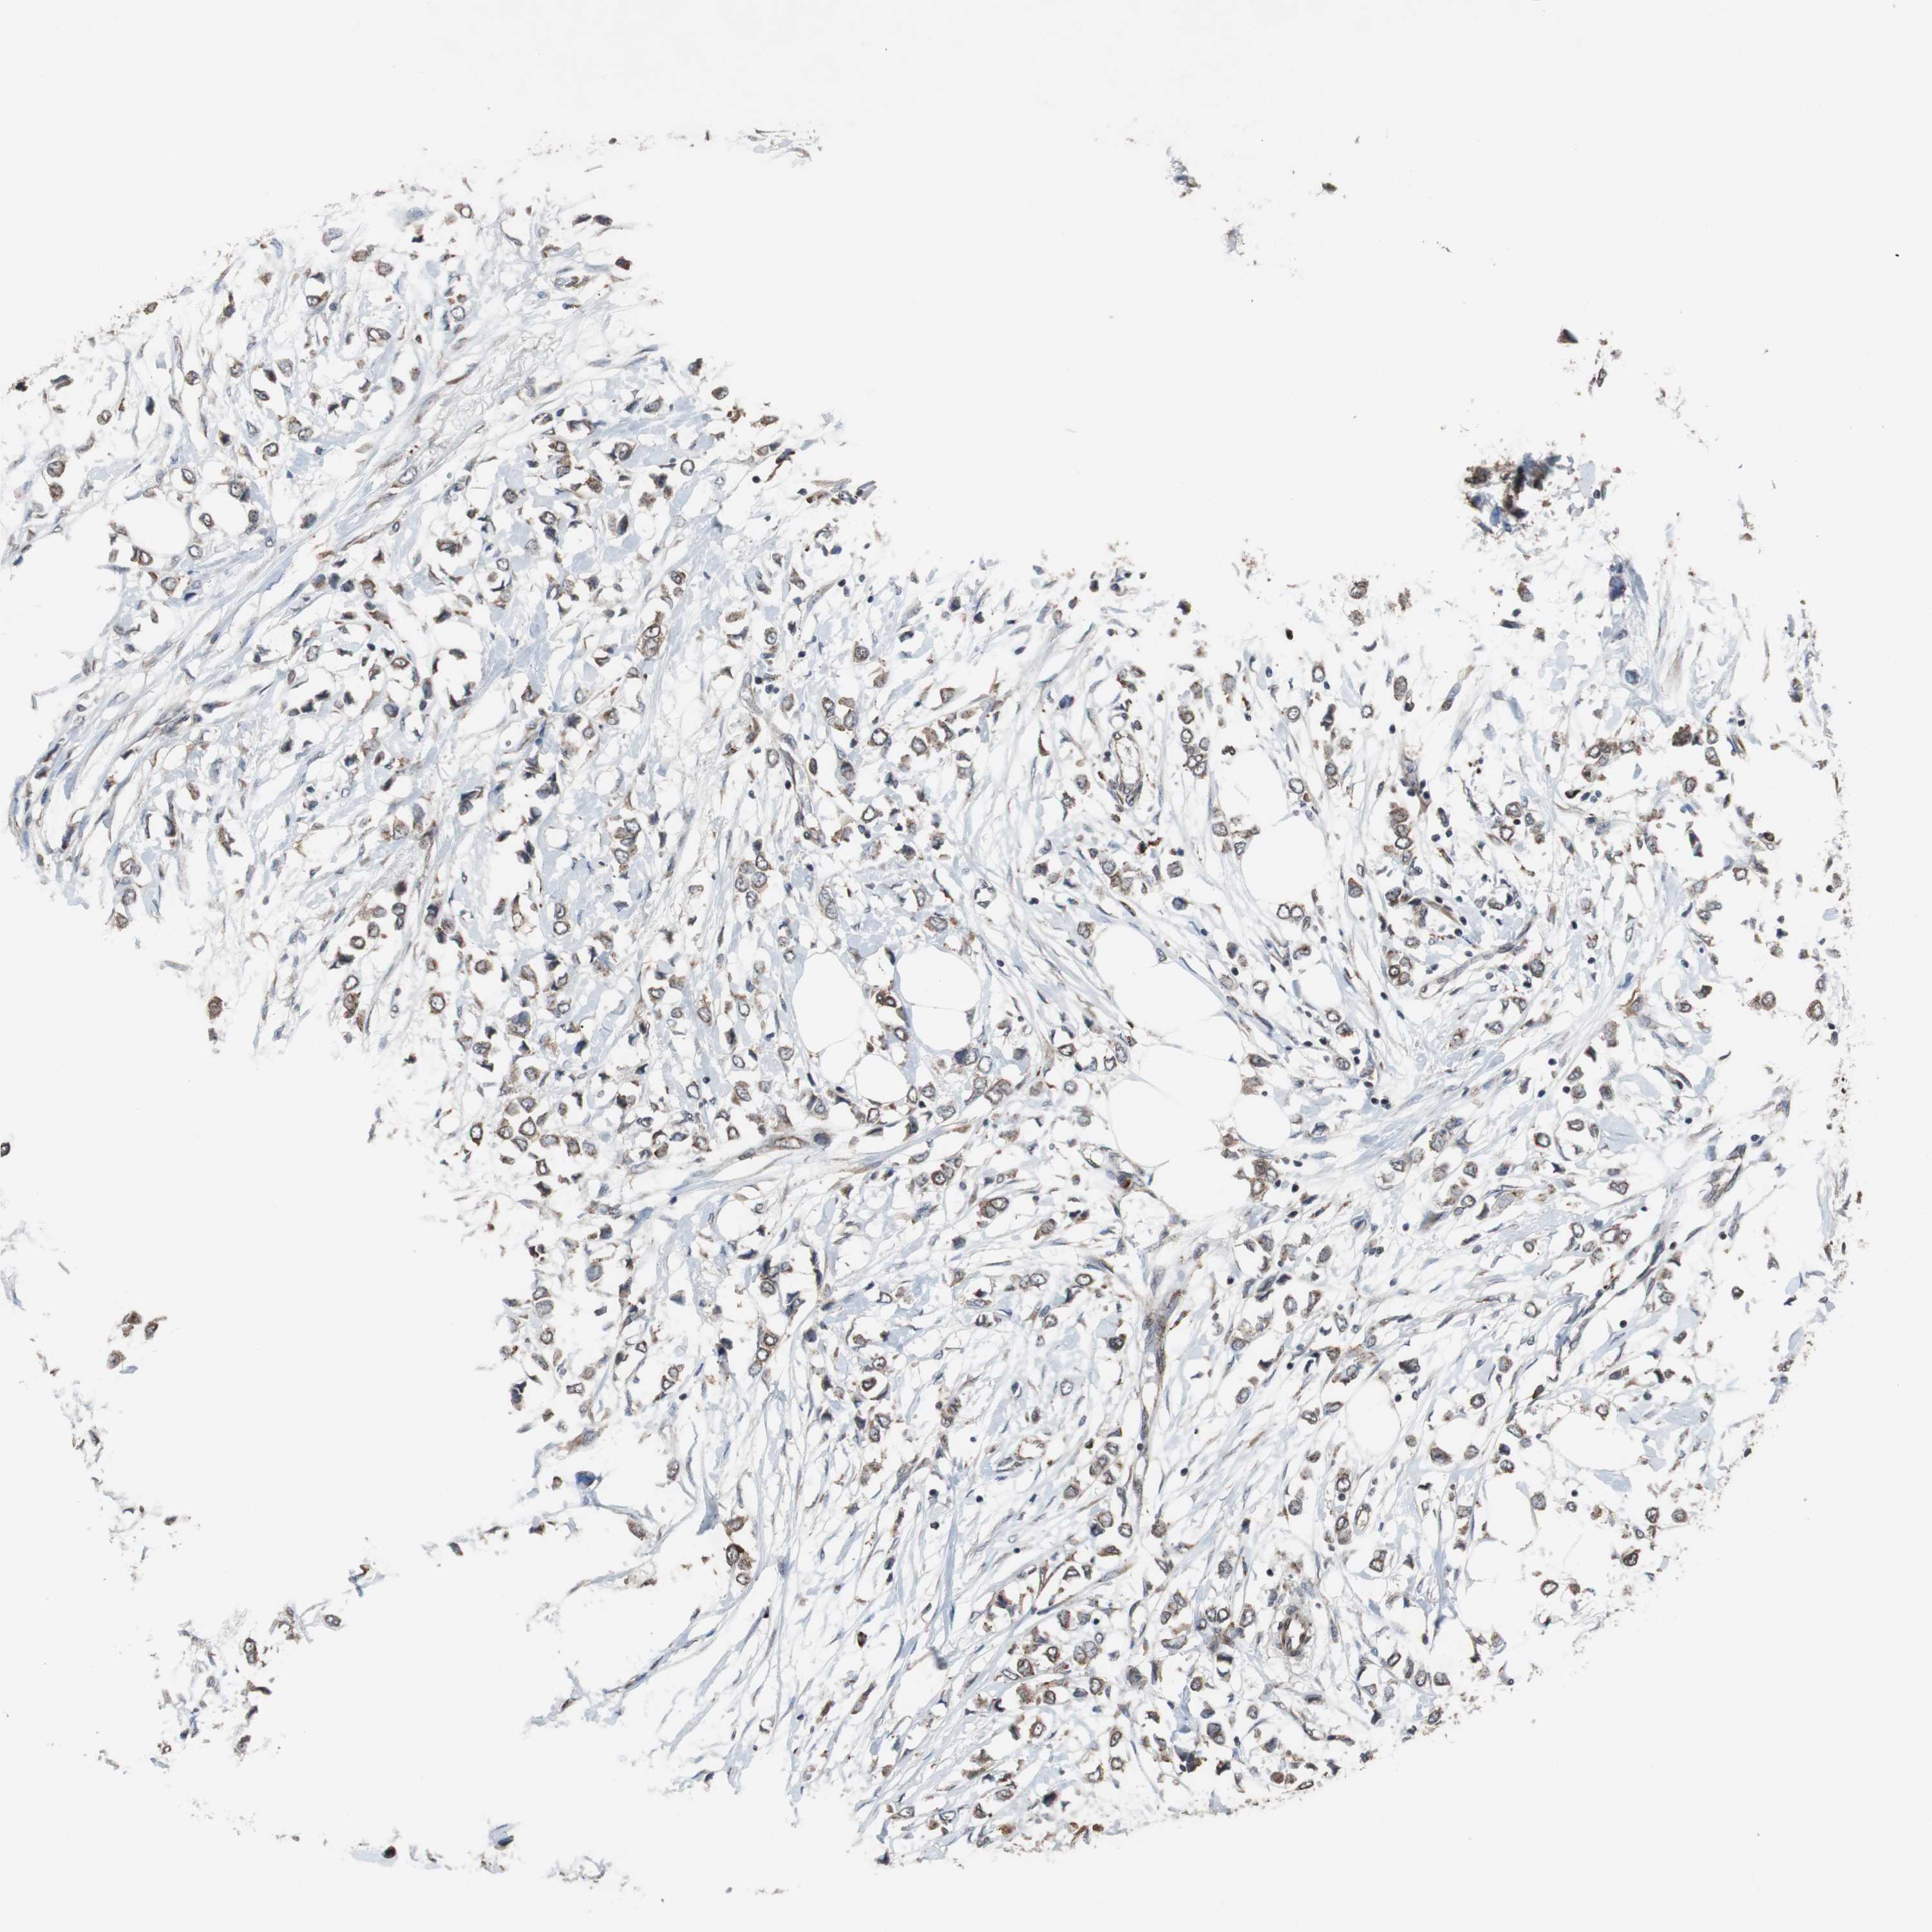

CANCER BREAST CANCER Show tissue menu

BRCA TCGA BRCA VALIDATION PROTEIN EXPRESSION